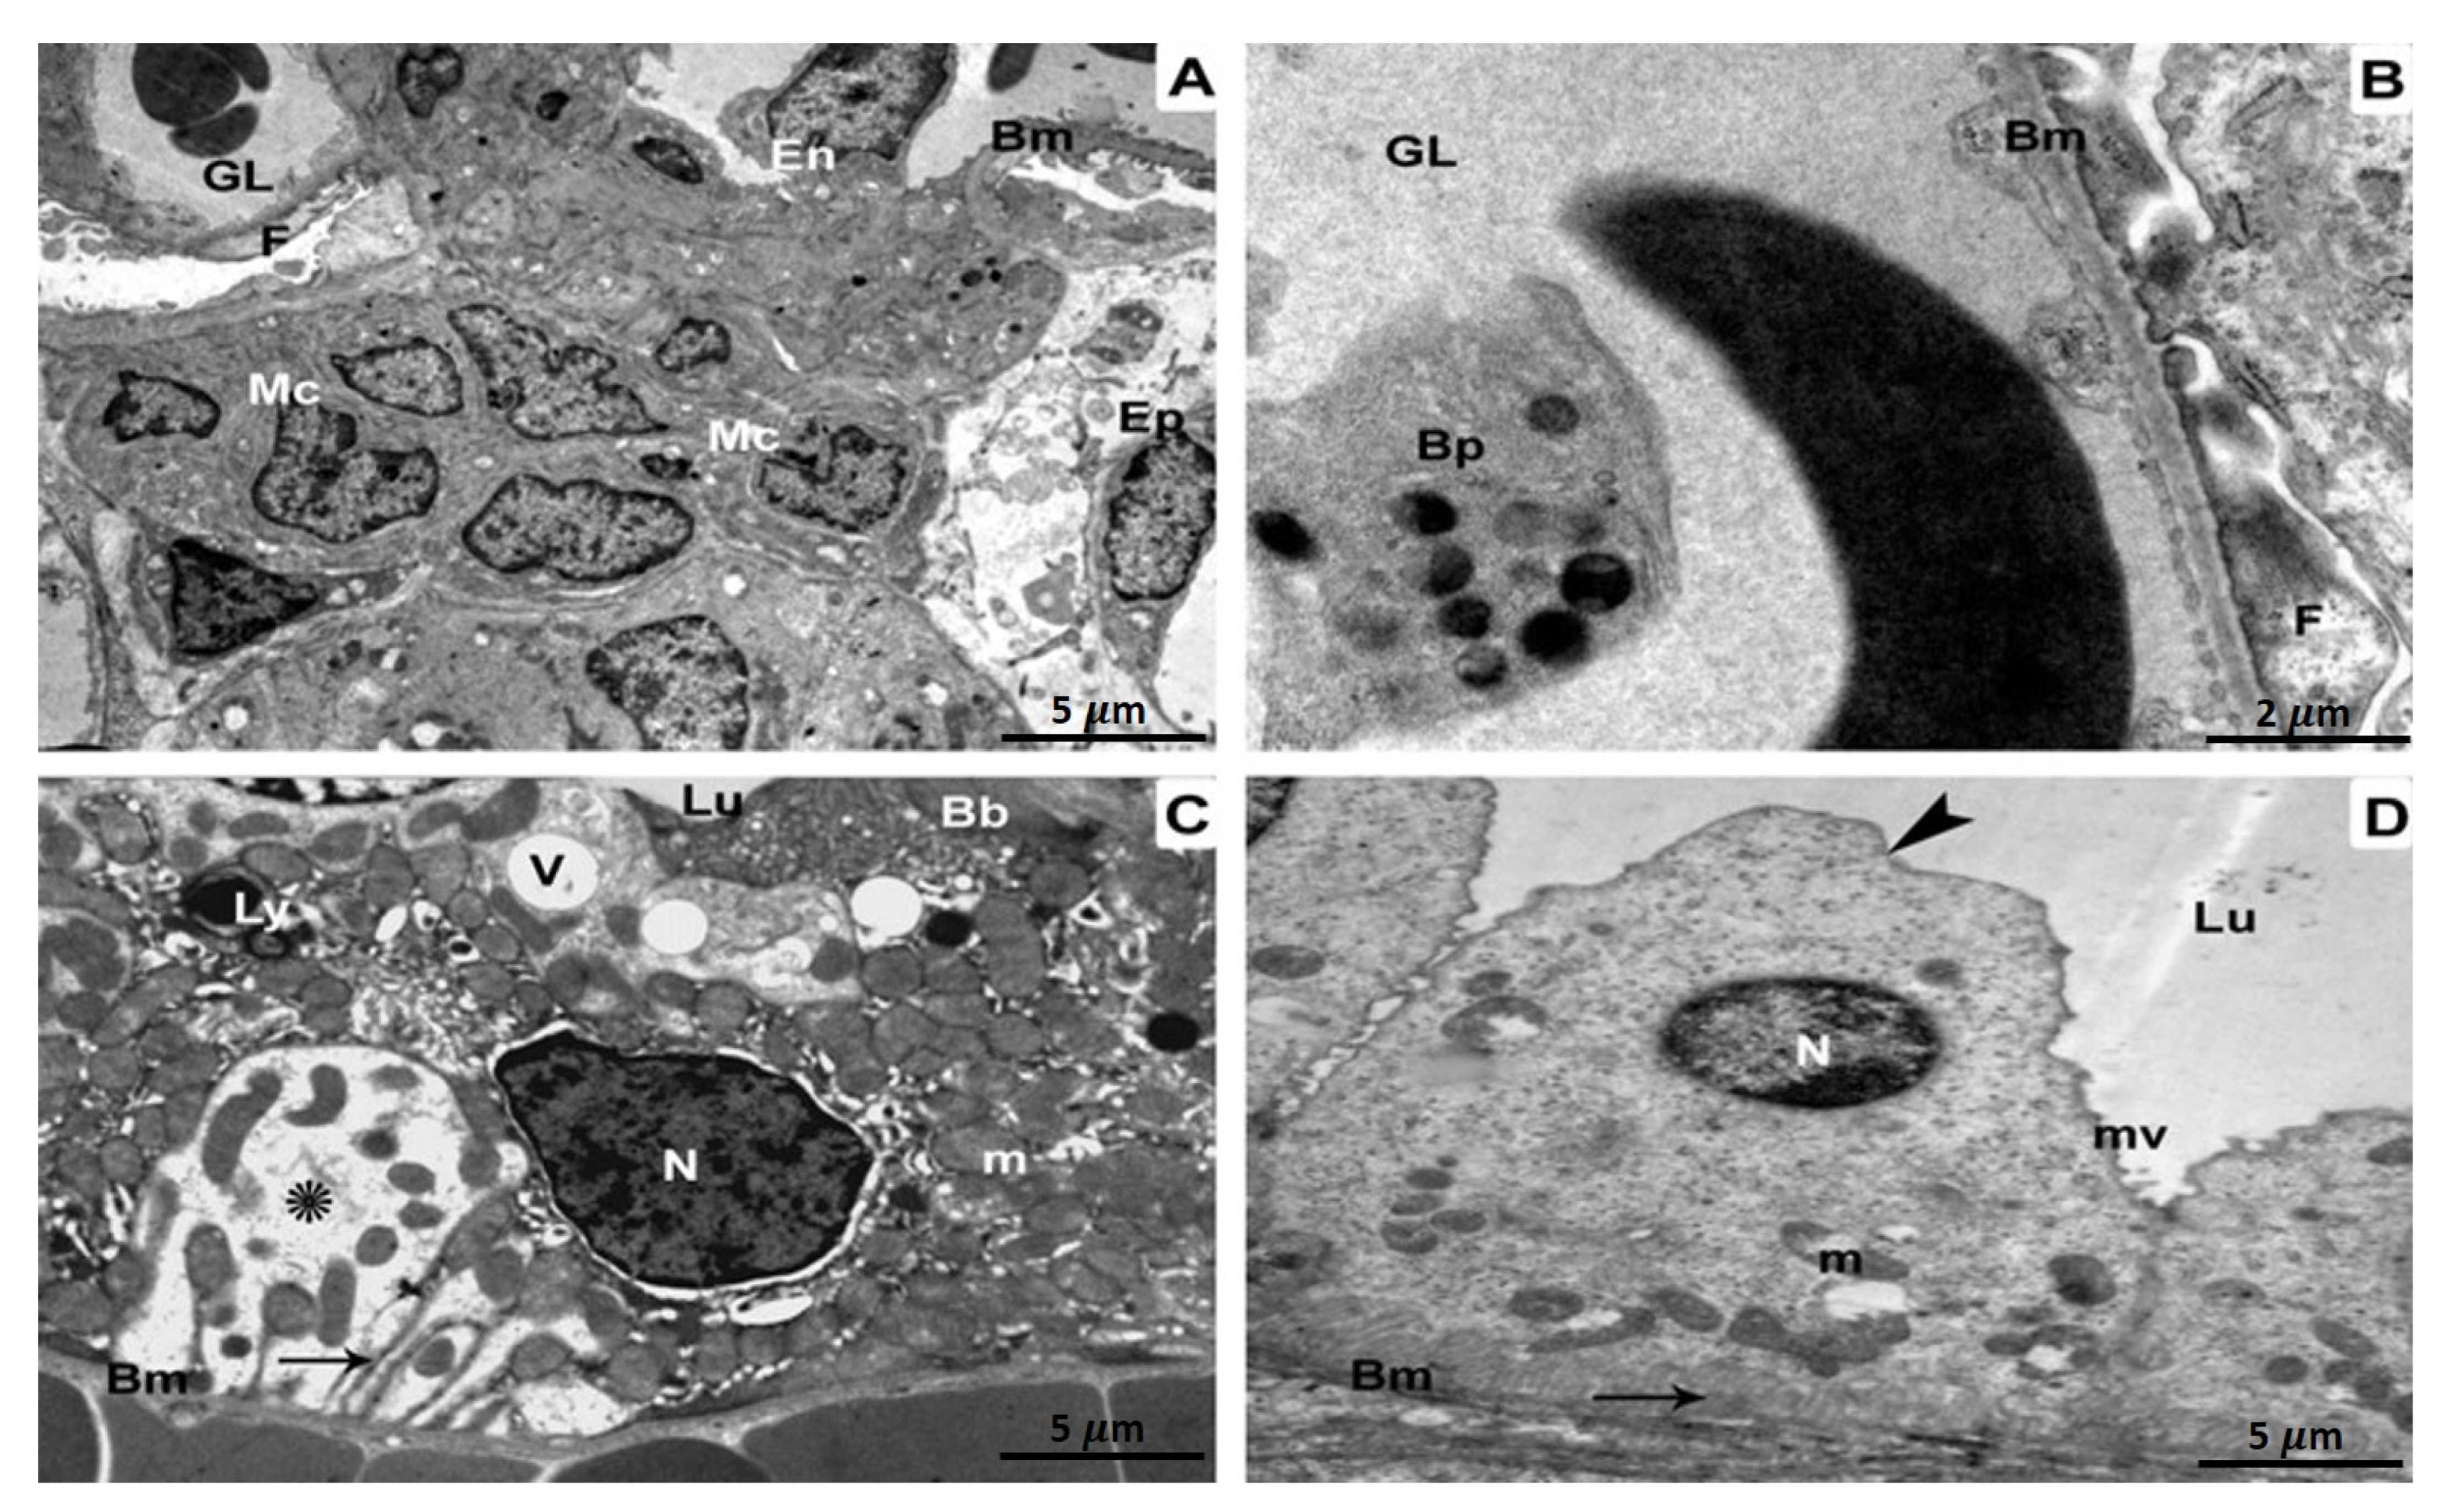

Kidney specimens of the control, as well as ATX-treated rat groups, exhibited a regular glomerulus with its basement membranes, capillary endothelium, and mesangial cells, in addition to podocytes with their foot processes (Figure 2A). Relatively high magnification showed the three glomerular basement membrane layers: an inner layer (lamina rara interna), an exterior layer (lamina rara externa), as well as a middle layer (lamina densa) containing thin diaphragms (Figure 2B). In a proximal-convoluted tubule cross-section, the epithelium tissue that lines the tube and resting on the basement membrane were observable. Inside the tubule, there were also brush-border microvilli, regular mitochondria, a perfectly intact nucleus, as well as basal infolding membranes (Figure 2C). Epithelium with small microvilli, undamaged mitochondria, a typical nucleus, in addition to infolding membranes were seen in a distal-convoluted tubule cross-section (Figure 2D).

Figure 2. Kidney specimens of the control group are depicted in TEM as follows: (A) A glomerulus with glomerular capillaries (GL), basement membranes (Bm), endothelium (En), mesangial cells (Mc), podocytes (Ep), as well as foot processes (F). 5 µm scale bar; (B) A more in-depth view of the glomerular basement membrane (Bm) revealing its three distinct layers: lamina rara interna, rara externa, and densa. Foot processes (F), fenestration (arrow heads), thin diaphragms (arrows), as well as podocytes (Ep) are all illustrated (Ep). At 2 µm scale bar, section (C) of a proximal convoluted tubule reveals cuboidal epithelial cells (Ep) resting on the basement membrane (Bm) and the tubular lumen brush border (Lu) (Bb). The nucleus (N), mitochondria (m), in addition to infolding membranes are all distinguished characteristics (arrow). 5 µm scale bar; (D) A section through a distal convoluted tubule revealing cuboidal epithelial cells (Ep) resting on a basement membrane and displaying short microvilli (mv) (Bm). The infolding membranes, the nucleus, and the mitochondria are all prominent characteristics (arrow). 5 µm scale bar.